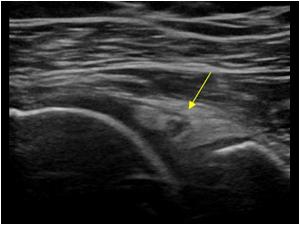

Rotator Cuff Tear

Supraspinatus Tear